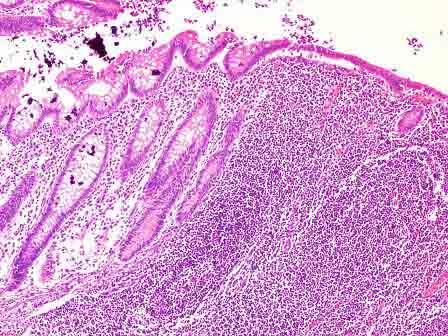

问题 患者女性,35岁,右下腹隐痛1个月,既往有阑尾炎发作史,经保守治疗控制。切除阑尾送检,镜下如图所示,应诊断为 ( )

选项 A.急性蜂窝织性阑尾炎 B.坏疽性阑尾炎 C.慢性阑尾炎 D.阑尾脓肿 E.阑尾腺瘤

答案 C